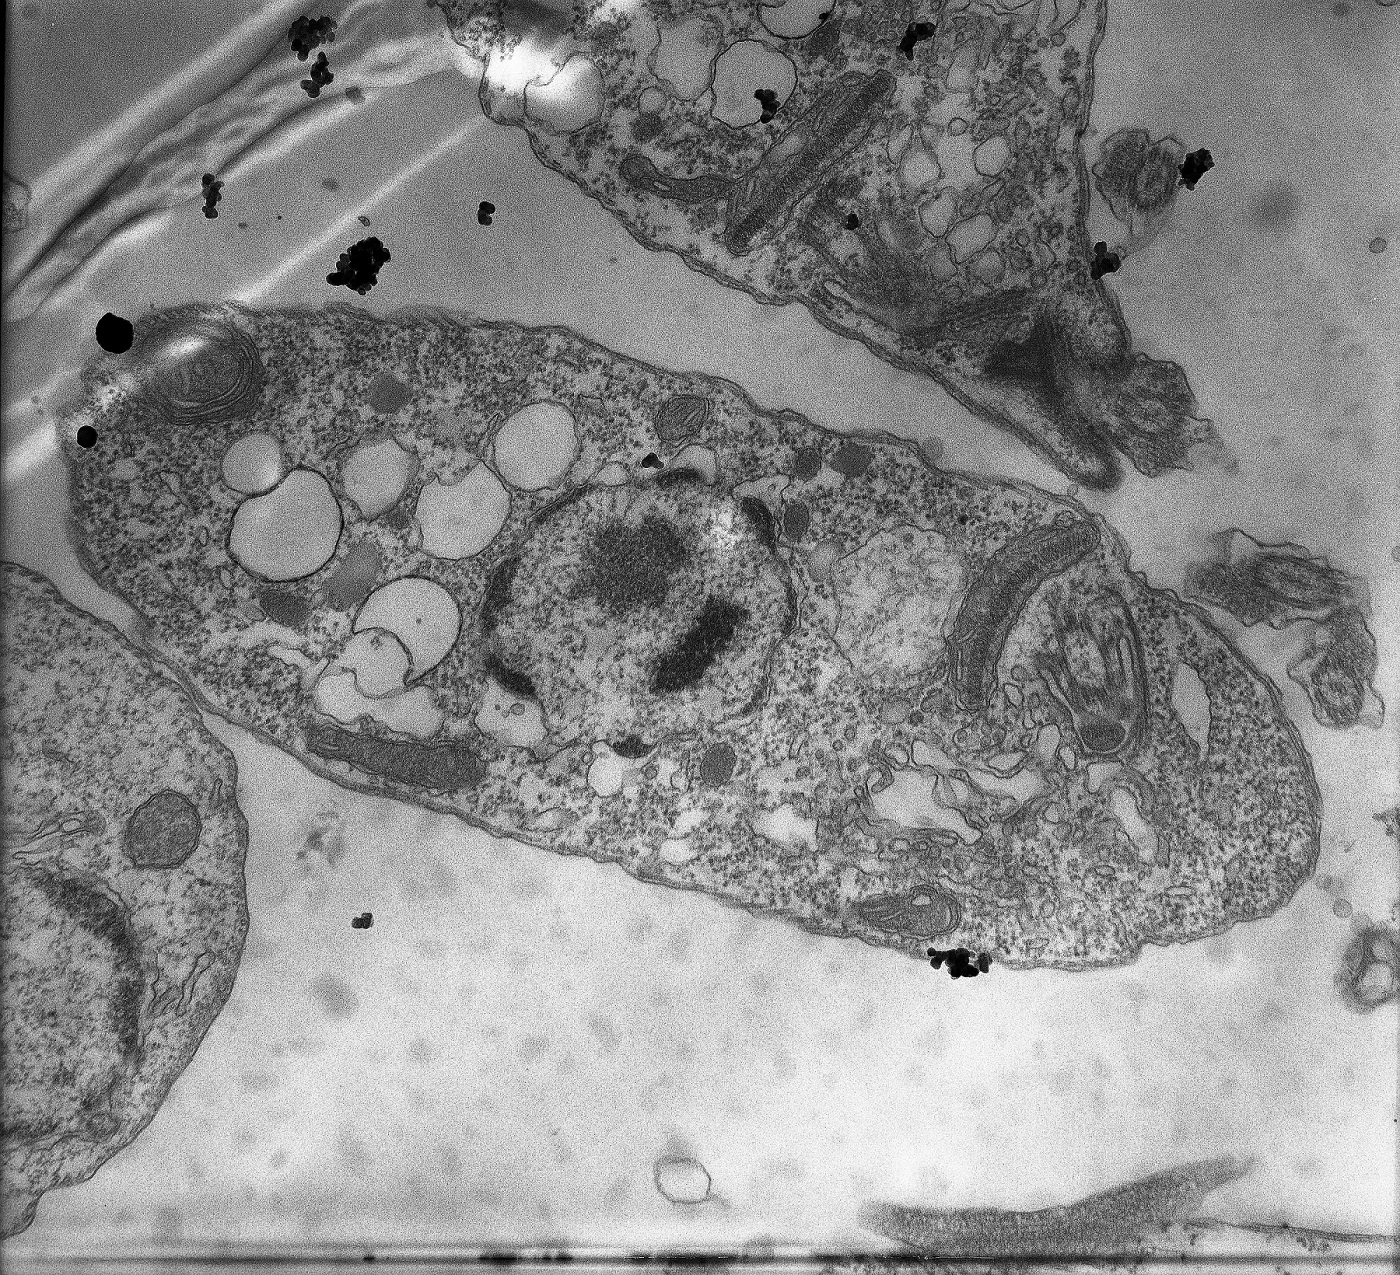

Describen un “arsenal silencioso” de la leishmaniasis visceral

La enfermedad puede ser mortal en más del 90 % de los casos si no es tratada oportunamente